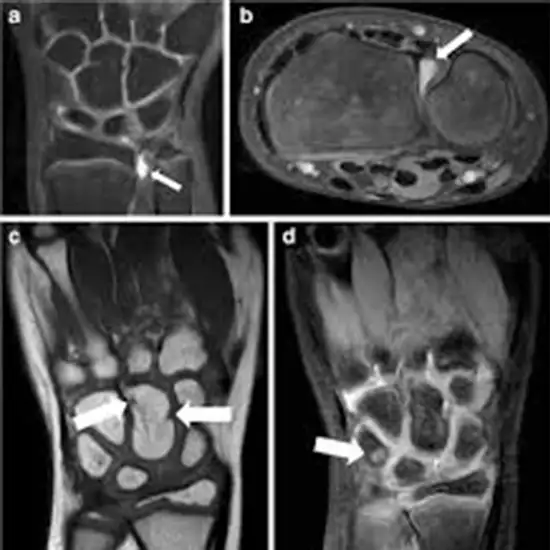

An MRI of the Wrist joint makes it possible to see the bones of the wrist joint and the tendons, ligaments, muscles, and blood vessels surrounding it. The wrist joint comprises the lower ends of the forearm bones and eight small bones called carpal bones (radius and ulna).